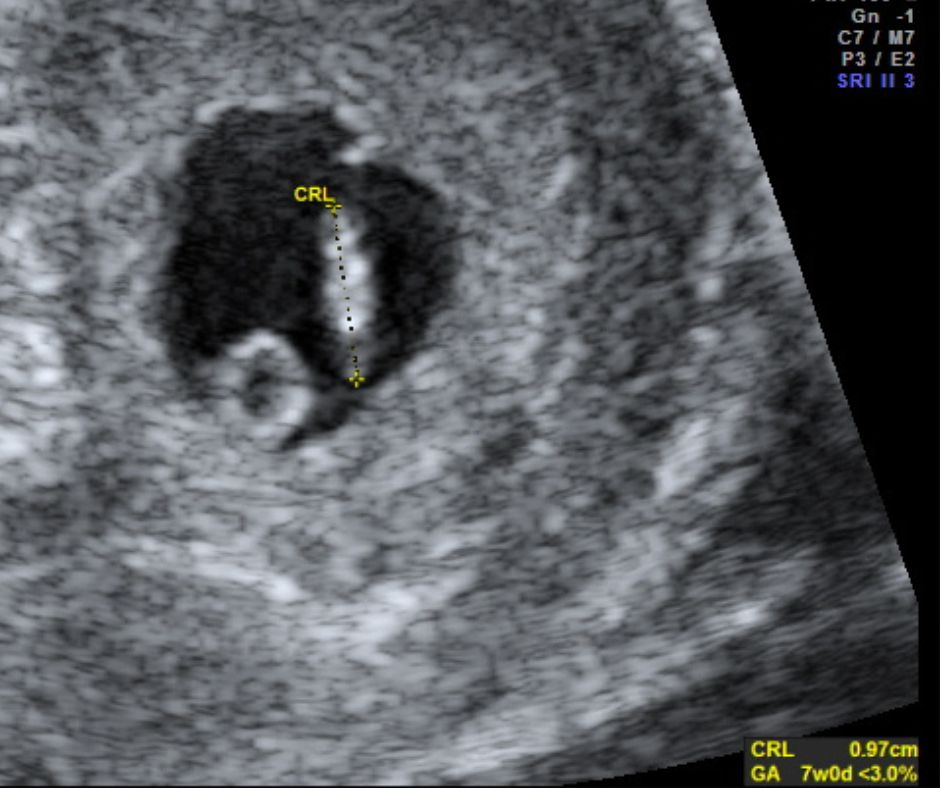

At the early stage - 6-13 weeks - it is possible via the ultrasound to:

see if the foetus is in the right position give a more accurate dating (than the pregnancy test/calculator)

identify if it’s a single baby or twins detect a heartbeat

ascertain if the pregnancy looks “safe” prepare a detailed report of findings to take away

During the scan you will be able to see the pictures of the tiny foetus on the big screen. The sonographer will show you as much as possible and capture a number of images. You will be offered two souvenir photos from the scan and the rest will be on a USB.

The quality of the visual result of the scan is dependent on the stage of pregnancy, the size and position of the baby, the volume of amniotic fluid and the amount of tissue (skin, muscle, etc) between the ultrasound probe and the foetus in the womb. A good image cannot always be obtained.